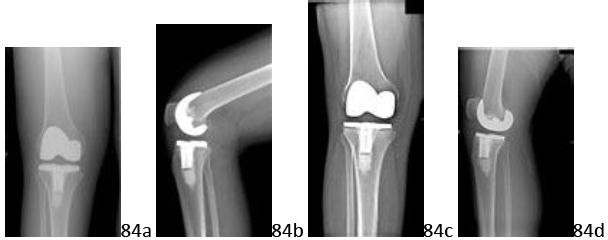

2. # Figure 4 shows the radiograph of a 65-year-old patient who is undergoing right total knee arthroplasty. After performing bone resections for a posterior cruciate-substituting femoral component, you note that both the flexion and extension gaps are tight in the lateral compartment. Which of the following structures should be released

first?

DISCUSSION: For patients with tightness in both flexion and extension, the lateral collateral ligament should be released before the other lateral structures. Soft-tissue balancing after correction of a

valgus deformity is performed to equalize varus and valgus laxity in both flexion and extension. If it is released after the other stabilizers (iliotibial band, posterolateral capsule, or popliteus tendon), the magnitude of these corrections will be more significant. This may lead to a greater flexion-extension asymmetry if an isolated extension or flexion release has been performed first. Release of the posterior cruciate ligament has the greatest impact on lateral knee balance, so the decision to use a cruciate retaining or substituting implant ideally should be made before proceeding with release of the lateral structures. An isolated flexion contracture is typically approached with a posterolateral capsule release. An isolated extension contracture may be treated with either a release of the iliotibial band or popliteus tendon. However, authors recently have indicated a preference for retention of the popliteus tendon. The Preferred Response to Question # 4 is 2.